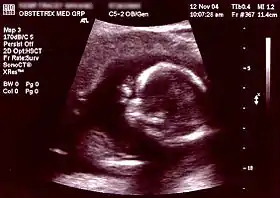

![]() Obstetric sonogram of a fetus at 16 weeks. The bright white circle center-right is the head, which faces to the left. Features include the forehead at 10 o'clock, the left ear toward the center at 7 o'clock and the right hand covering the eyes at 9:00. | |